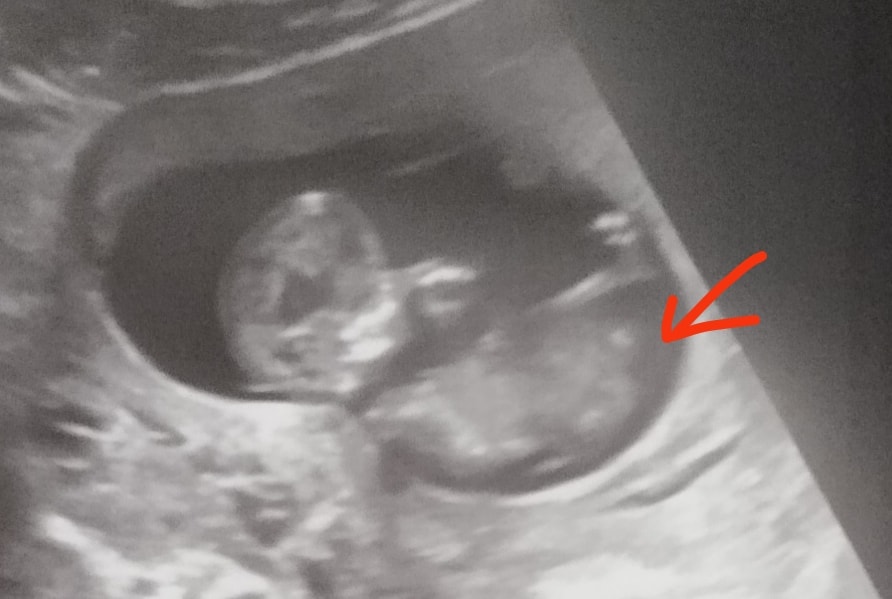

София в Клуб беременных 7 месяцев Погадайте на пол🤌 Пол малыша Это половой бугорок? Если да, то кого видите?:) 🤔 Мальчик 37.8% Девочка 14.6% Не понятно 47.6% Голосовать 82 голоса Посмотрите еще 20 записей на эту тему Лучший ответ Илина 55% девочка😉 30.04.2025 Ответить Отменить Ответить Айна А Мальчик 30.04.2025 Ответить Так какой же пол?😁 Мальчик или девочка в 16 недель и 6 дней. Чаты Беременных Выберите чат: Январята-2026 Февралята-2026 Мартята-2026 Апрелята-2026 Майчата-2026 Июнята-2026 Июлята-2026 Августята-2026